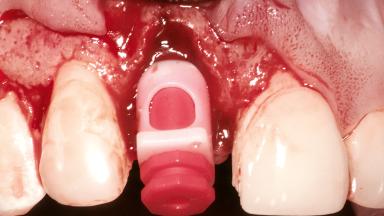

A healthy 26-year-old woman was referred for evaluation and treatment of her failing maxillary right central incisor (tooth 11). She reportedly traumatized the tooth at about age 9 and subsequently had repeated conventional and surgical endodontic procedures and fixed restorations. Despite these procedures, she had recurrent fistulas in the apical mucosa and a mid-facial pocket of 7 mm with suppuration. All other sites on the tooth probed 3 mm without inflammation. She presented with a medium biotype with triangularlyshaped teeth and a moderately high smile line, showing all of her papillas and a few millimeters of marginal gingiva in a full smile.Ceramic veneers were present on teeth 12, 21, and 22, and they were known to be somewhat bulky, eventually requiring replacement. She had a strong desire to avoid additional tooth preparation and would not consider a fixed dental prosthesis to replace tooth 11.

Bone Augmentation | Horizontal|Simultaneous |

Augmentation Materials | Autogenous chips|Membrane |

Soft Tissue Grafting | Simultaneous |